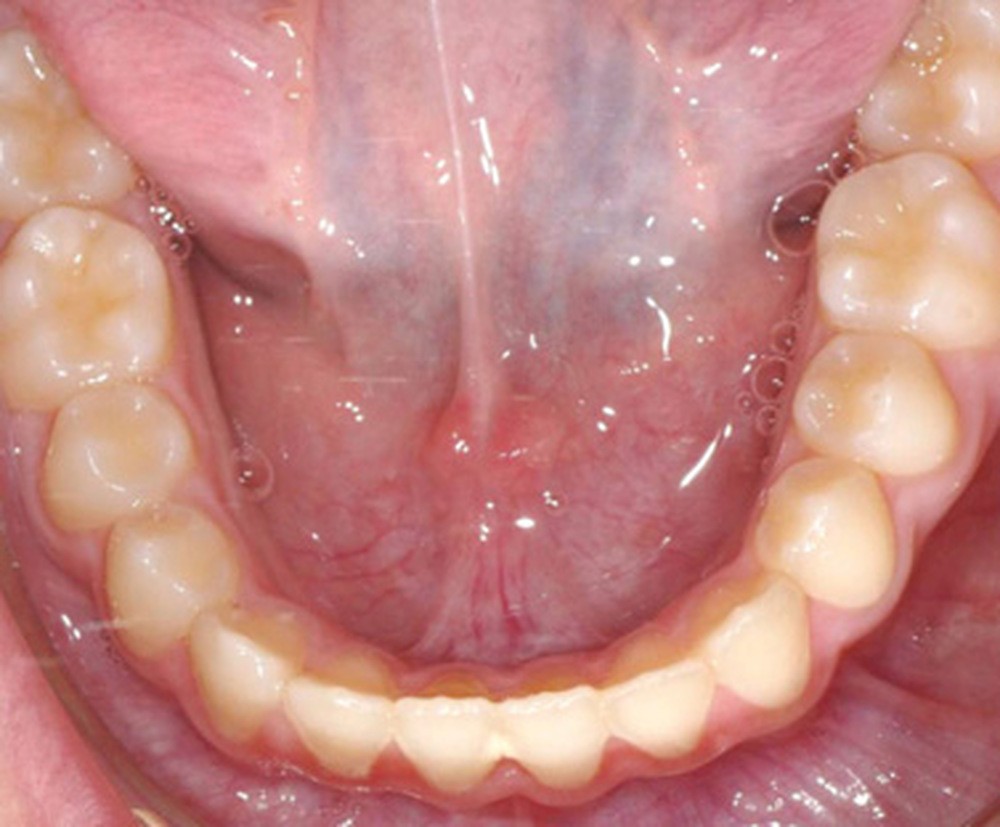

Quelques années plus tard, au moment de démarrer sa prise en charge orthodontique, la patiente présentait à nouveau une béance antérieure, un décalage des milieux incisifs de 2 mm et le problème transversal avait récidivé. Lors de l’examen clinique, elle présentait un inversé d’occlusion bilatéral postérieur et une ventilation buccale exclusive. À la suite du refus de réaliser l’amygdalectomie de façon précoce, elle ronflait toujours et sa déglutition ne s’était pas modifiée malgré des séances d’orthophonie (fig. 7 à 15).